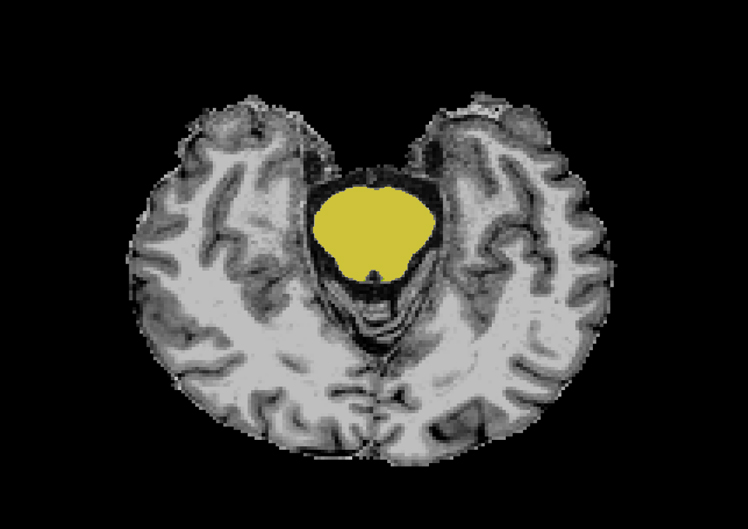

His current research focus is to study Iron overload in Substantia Nigra (SN) using Quantitative Susceptibility Mapping (QSM) and R2* mapping and to quantify Substantia Nigra (SN) damage in Idiopathic rapid eye movement.....